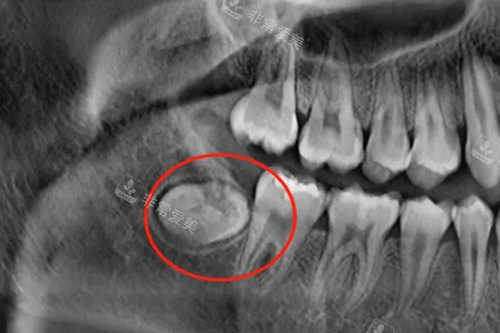

智齿,很多时候由于生长位置不正,容易引发智齿冠周炎等一系列问题,给患者带来疼痛和不便。

而残根则是牙齿因病或外伤等原因折断后残留的部分,不仅影响口腔卫生,还可能导致炎症。

这两种情况的拔牙属于治疗性质,符合对于疾病治疗费用报销的范畴。